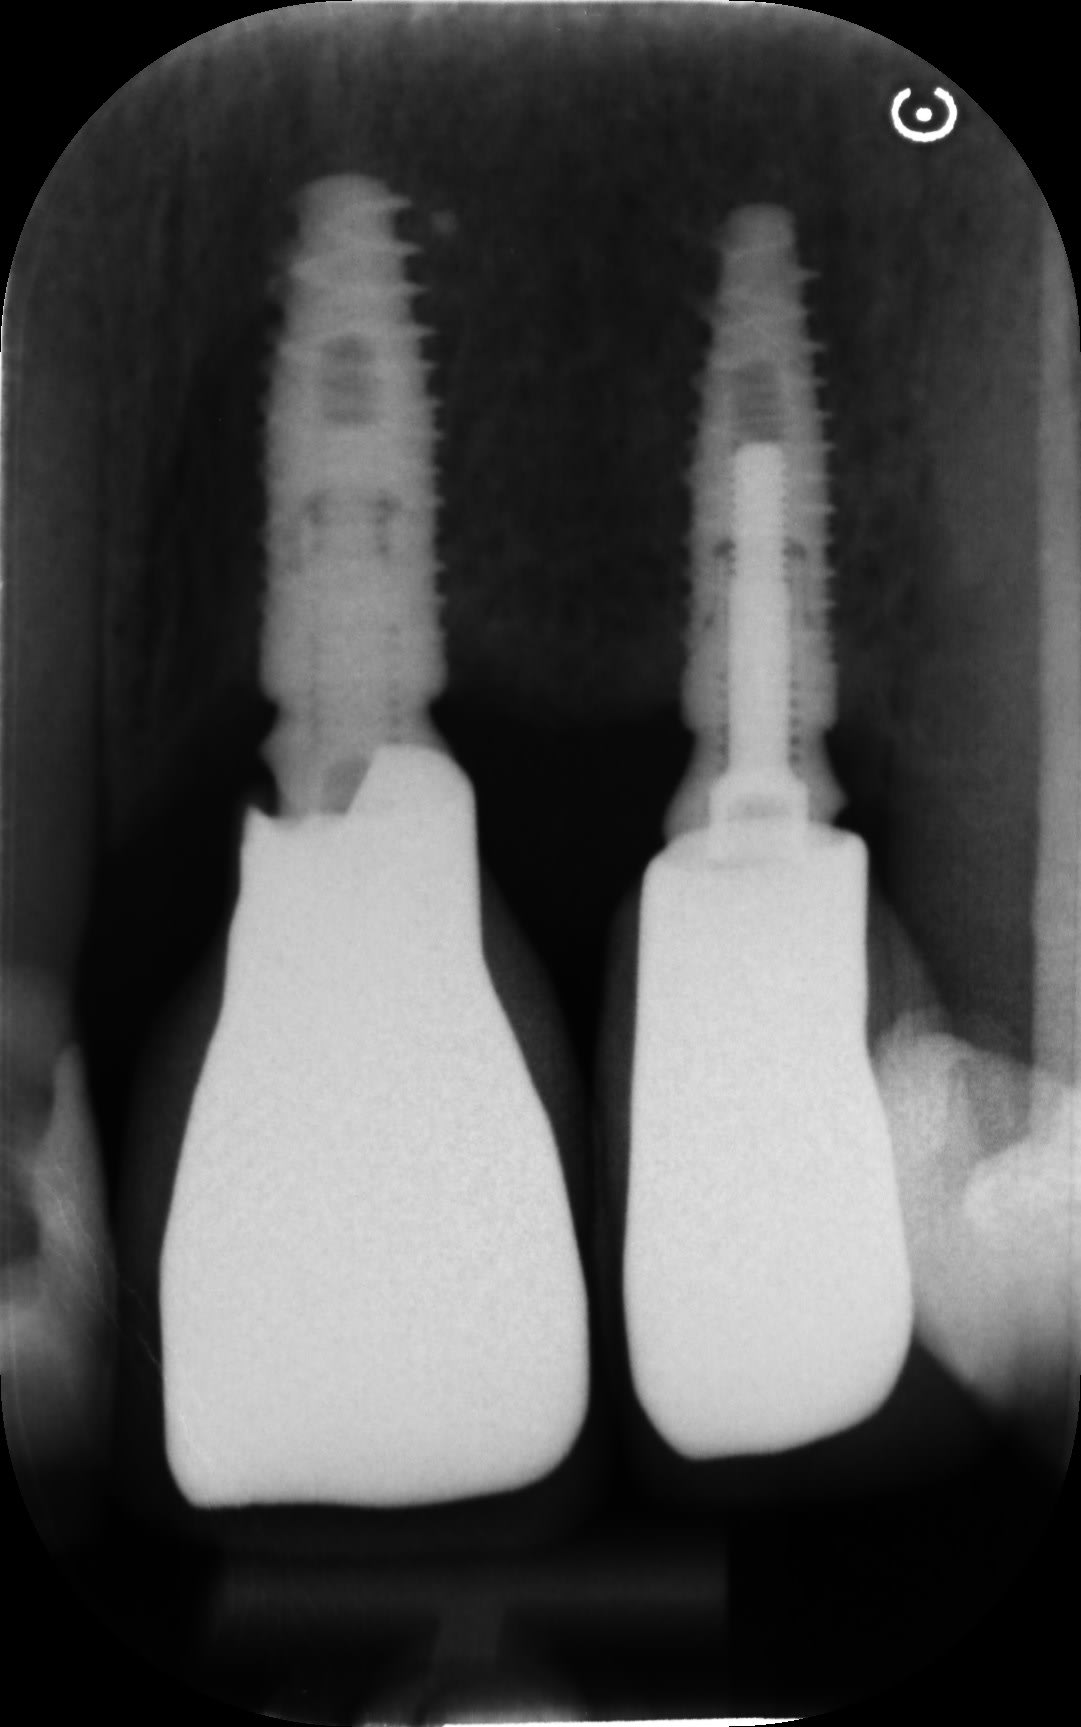

je ne connais pas ces implants, pouvez-vous m'aider, pour les implants 21/22/14?

Kontact Biotech pour les 2 incisives

il y a 2 straumann pour les 15/16....14 pas encore trouvé

14 je pense TBR oct in